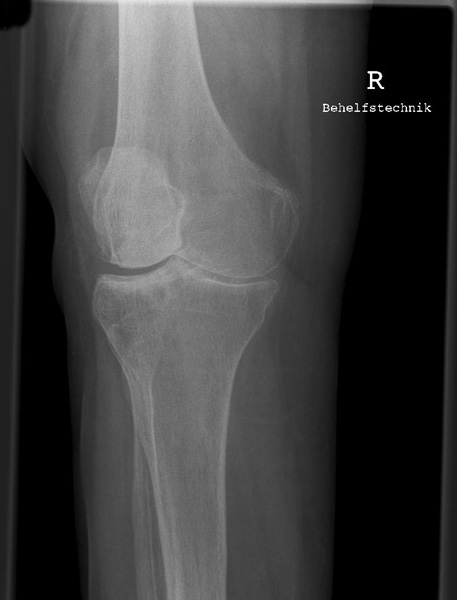

Kniegelenk

Knie a.p.

120_2.jpg

Fehler

Beide Gelenkfacetten des Tibiakopfes stellen sich oval dar, auf der einen Seite höher als auf der anderen; so kommt es im Röntgenbild zur Überschneidung mit den Gelenkkondylen des Femur und unter Umständen auch zu einer Verdeckung der Eminentia intercondylaris.

Abhilfe

Der Zentralstrahl muss bei jeder Knieaufnahme, sei es bei gestrecktem oder gebeugtem Knie, immer senkrecht auf die Längsachse der Tibia treffen.